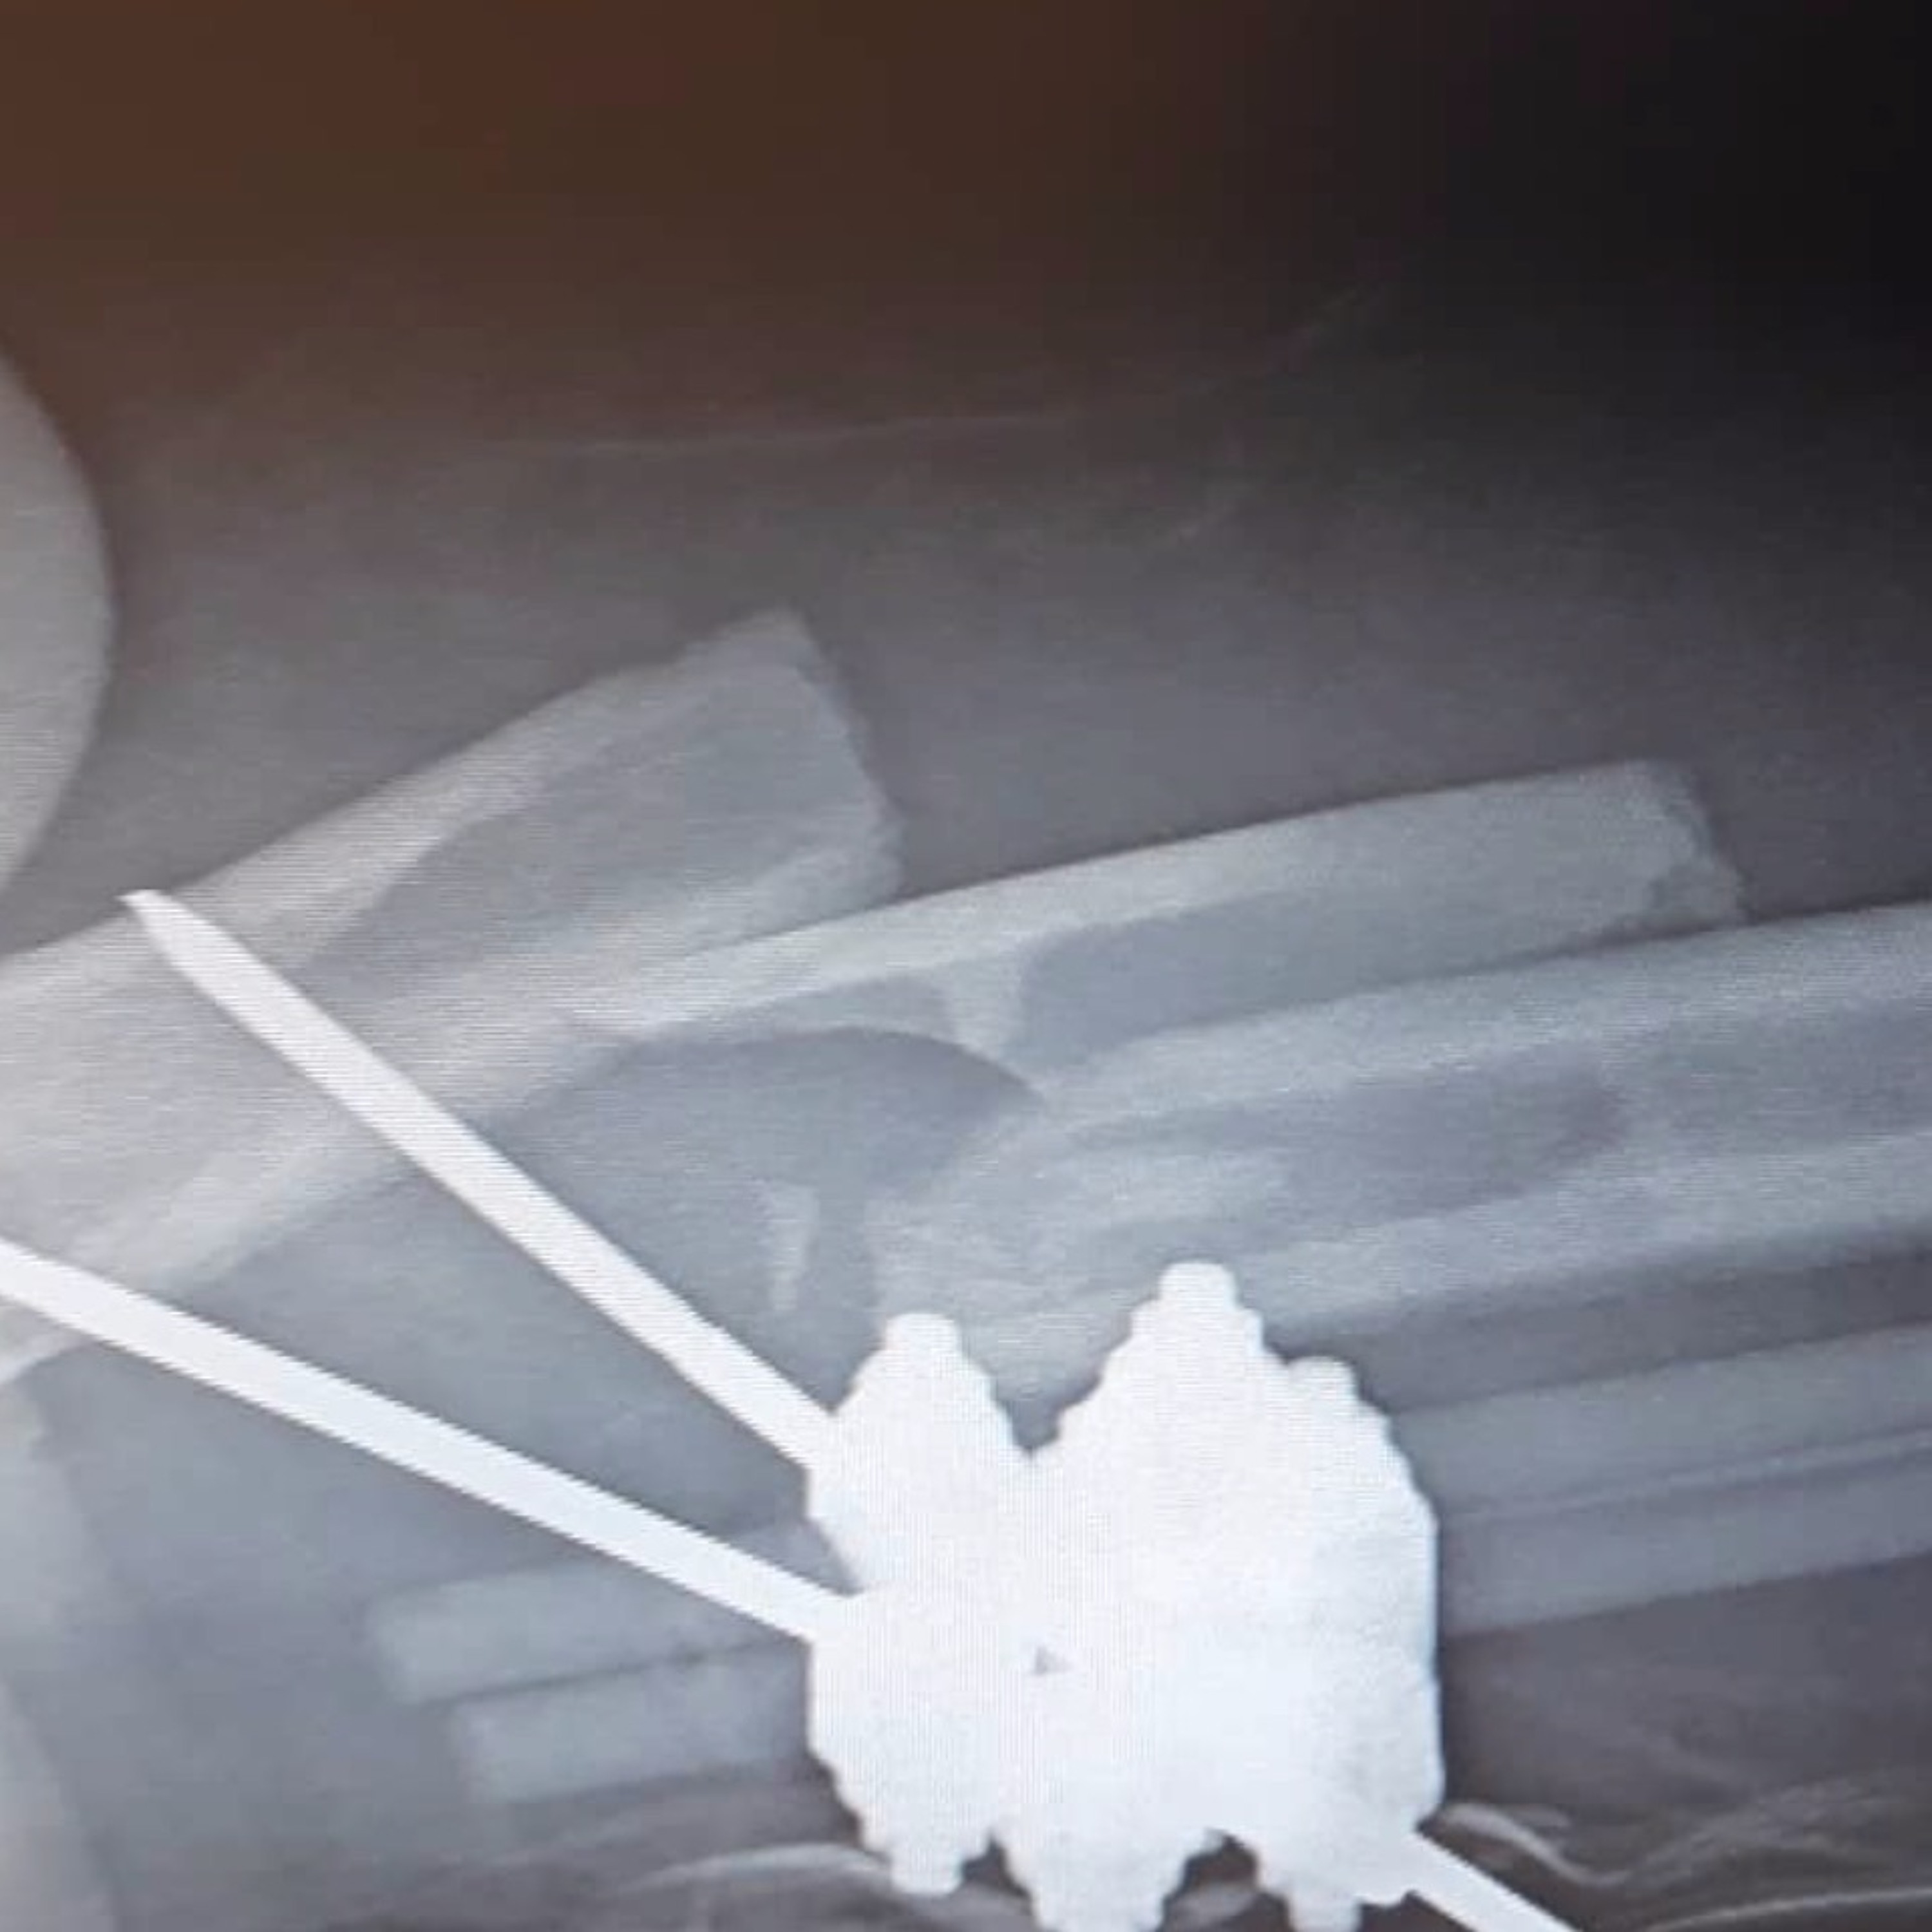

Hey everyone welcome to episode 065. This week we got to hangout with James Henry (@slimjim11x)and dive a little into riding mopeds and crazy wrecks.